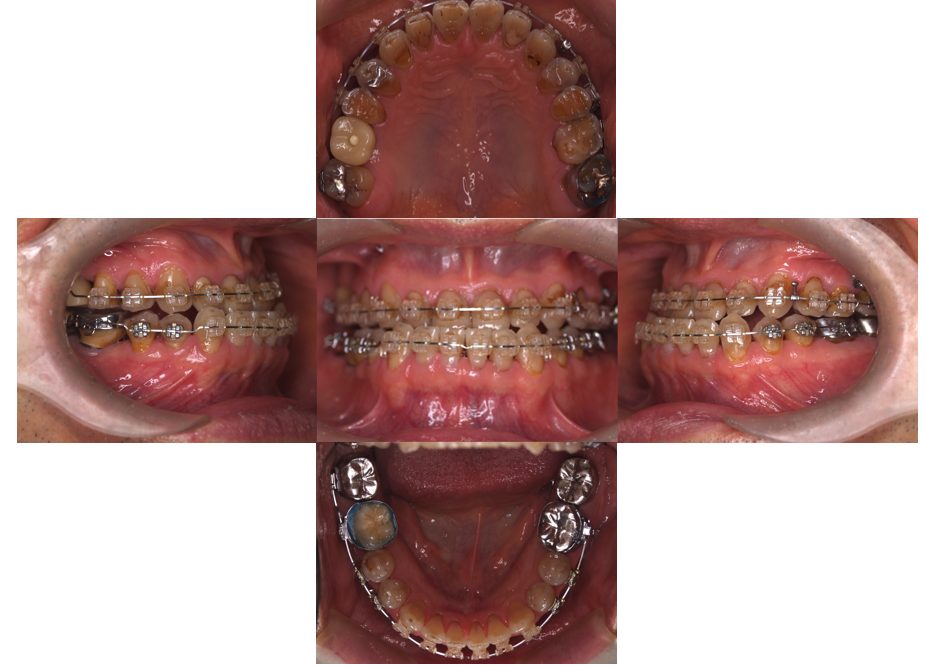

| 主訴 | 20代女性 矯正治療希望。治療途中の歯もあるので治したい。左顎関節が痛い。 |

| 治療内容 | 矯正治療を行いました。 |

| 治療費 | 1,400,000円(税込み) |

| 治療期間 | 3年(矯正治療期間 2年半) |

| 治療回数 | 40回 |

| 想定されたリスク | 顎骨の変形があったので、全身麻酔下による外科処置が必要になり、身体的、精神的負担が増す可能性がありました。 清掃状況によっては矯正中にむし歯が発生するリスクがありました。 |